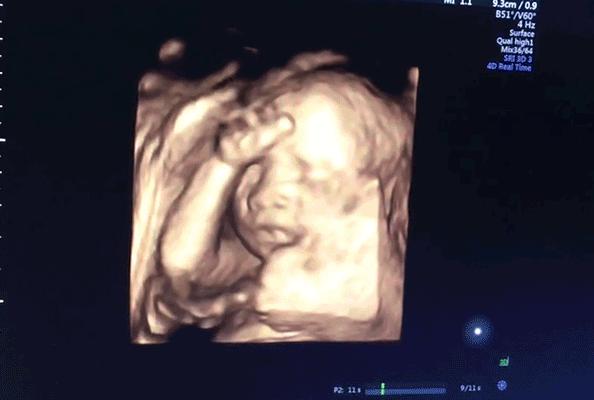

百忙之中的老公难得请假陪DayDay子一起做四维彩超,

看到超声影像里的画面,

一脸慈父笑容的老公努力跟医生套话:“这个崽长得帅还是漂亮?”

超声医生一本正经的回答:“五官端正!”

笑崩了的DayDay子才知道原来老公也有如此孩子气的一面。